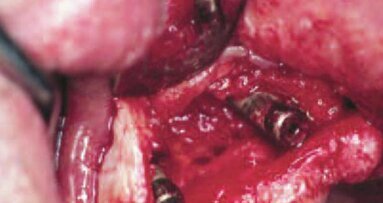

Jednym z możliwych rozwiązań jest zastosowanie hybrydowych wkładów koronowo-korzeniowych składających się z dopasowanych ćwieków z włókna szklanego w połączeniu z osobno przygotowywaną nadbudową ceramiczną (Ryc. 1). Takie rozwiązanie oferuje możliwość dostosowania koloru wkładów do koloru filarów protetycznych przy jednoczesnym znaczącym wzmocnieniu ich struktury naddziąsłowej. Nadbudowa ceramiczna przygotowywana jest w pracowni protetycznej, razem z miejscem przechodzenia ćwieka z włókna szklanego (Ryc. 2). Takie rozwiązanie wymaga bardzo starannego dopasowania całości na modelu, jak również w czasie przymiarki w ustach u pacjenta. Możliwe jest jednak takie przygotowanie nadbudowy ceramicznej, aby jej „kołnierz” częściowo wchodził w głąb korzenia zęba razem z ćwiekiem z włókna szklanego (Ryc. 3).

Wkłady o takiej konstrukcji wymagają odpowiedniego postępowania przy cementowaniu, które musi wykorzystywać cementy kompozytowe. Sam ćwiek z włókna szklanego powinien zostać odtłuszczony oraz potraktowany silanem dedykowanym do materiałów kompozytowych lub uniwersalnym (Ryc. 4). Ceramiczny element nadbudowy przygotowywany jest przy pomocy trawienia kwasem fluorowodorowym oraz aplikacji silanu dedykowanego do ceramiki (lub również uniwersalnego, Ryc. 5).

Niezwykle istotna jest kontrola dopasowania w ustach u pacjenta przed cementowaniem i zachowanie jednoznacznego toru osadzania całej konstrukcji, gdyż później cement przysłoni wiele szczegółów na łączeniu brzeżnym (Ryc. 6). Do kanału korzeniowego wprowadzany jest cement kompozytowy podwójnie wiążący z wyraźnym nadmiarem, a następnie wprowadzamy ćwiek z włókna szklanego, aby równomiernie rozprowadzić cement po wszystkich powierzchniach korzenia (Ryc. 7). Potem należy usunąć ćwiek i osadzić na korzeniu nadbudowę ceramiczną. Zanim cement zwiąże, poprzez nadbudowę wprowadzić należy wkład z włókna szklanego i spozycjonować całość na filarze.

Po starannym oczyszczeniu całej konstrukcji z nadmiaru cementu, kolejnym etapem jest wstępna polimeryzacja światłem (Ryc. 8), ale po jej wykonaniu i tak należy zaczekać aż upłynie czas wiązania chemicznego cementu. Dopiero po tym czasie możliwe jest podjęcie dalszych czynności związanych z przygotowaniem filaru protetycznego do wycisku (Ryc. 9).

Wkłady koronowo-korzeniowe w zębach 12 i 22 zostały usunięte, a zęby ponownie przeleczone endodontycznie. Zdecydowano o zastosowaniu wkładów ceramicznych z ćwiekami z włókna szklanego, aby uniknąć kompromisów pomiędzy estetyką a przeziernością koron, tym bardziej, iż w sąsiedztwie zaplanowano wykonanie licówek ceramicznych. Zęby opracowano pod wkłady i wykonano wycisk (Ryc. 15). Gotowe elementy składały się z 2 części i wymagały opisanej powyżej procedury cementowania (Ryc. 16 i 17).